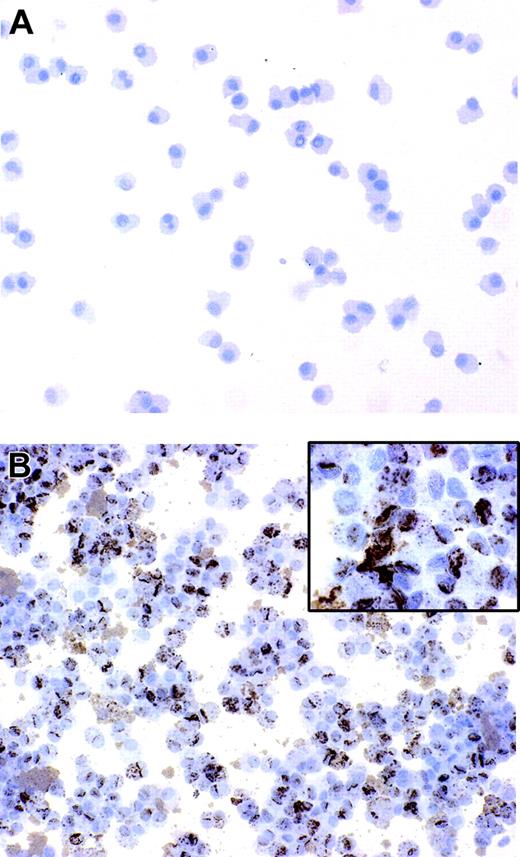

Immature DCs have an elevated intrinsic capability to internalize microbes and subsequently to differentiate into mature antigen-presenting cells.4 We have previously reported that B henselae is subjected to rapid internalization and survives in murine macrophages.25 In order to assess whether B henselae infects DCs, immature DCs were incubated with B henselae (bacteria/DC ratio 10:1) for 60 minutes. After gentamicin killing of extracellular bacteria, DCs were collected and subjected to cytospin and immunocytochemical staining by the use of anti–B henselae monoclonal antibody (anti-BH). We found that the majority of DCs (> 95%) that were incubated with bacteria were infected, as shown by the strong reactivity for anti-BH in their cytoplasm (Figure 1A-B). The staining was exclusively intracellular, with a granular cytoplasmic pattern of expression, suggesting that bacteria are internalized by DCs (Figure 1B inset).

B henselae infects monocyte-derived DCs. DCs untreated or infected with B henselae were stained with anti-BH. No reactivity is detectable in uninfected DCs (A), whereas the majority of infected DCs display a strong positivity (B) with a granular cytoplasmic pattern (B inset). Immunoperoxidase technique for anti-BH counterstained with Meyer hematoxylin. Original magnification, × 200 (A-B) and × 600 (B inset).

In order to investigate the effect of B henselae infection on DC maturation, we evaluated the immune phenotype of human DCs incubated for 24 hours with B henselae at a bacteria/DC ratio of 10:1; LPS was used as the prototype of a bacterial derivative that is known to induce full maturation of DCs. As shown in Figure 2, Bhenselae infection induced the expression of CD83 and CCR7 and the up-regulation of HLA-DR, CD80, and CD86 to levels comparable with those obtained with LPS. Next, we assessed the expression of CD208, a lysosomal protein induced in mature DCs subjected to stimulations such as LPS treatment. CD208 expression was evaluated by immunocytochemistry on cytospin preparations of B henselae–infected DCs (Figure 2B). The majority of infected DCs (more than 90%) displayed the typical CD208 paranuclear expression suggesting that B henselae constitutes a strong maturation stimulus for human DCs. Next, we investigated the consequences of DC infection by B henselae on the capacity of these cells to provide a costimulatory signal to normal allogeneic T cells. DCs matured by incubation with B henselae were able to induce the proliferation of allogeneic T lymphocytes at levels that were comparable to those attained with LPS-matured DCs (Figure 2C).